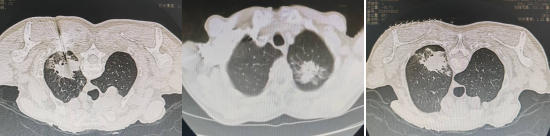

李某胸部CT影像

患者李某,81岁,反复咳嗽、咳痰、气短1个多月,痰为黄绿色,在当地医院接受抗生素治疗1个月余,症状未显著改善。胸部CT扫描可见左肺上叶带有毛刺的结节,不除外肿瘤。看到“肿瘤”二字,患者和家属有些害怕,前来我院就诊。

呼吸与危重症医学科主任戚刚强仔细查看CT影像后,考虑为特殊感染,结核的可能性较大。为明确诊断,主管医生皮磊与家属充分沟通后,行CT引导下经皮肺穿刺活检,过程顺利,从肺部“占位”中穿刺出6条肺组织,病理结合显示炎性肉芽肿,基因结果提示结核菌。该病相对容易治疗,得知是虚惊一场,患者和家属如释重负……